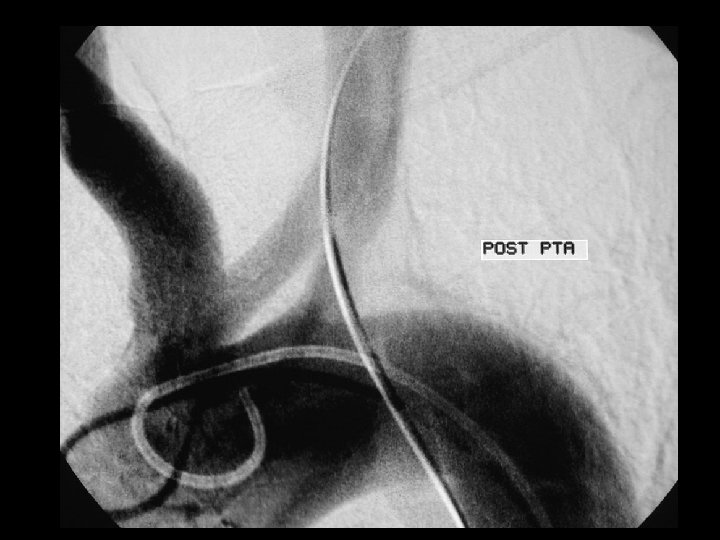

Subklavyan stenoz; PTA